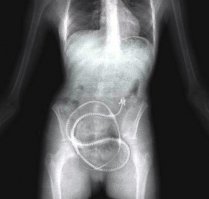

Рентген живота 91-летней Эстелы Мелендес, круглой опухолью которой оказался окаменевший плод, который она носила в своём животе в течение 60 лет